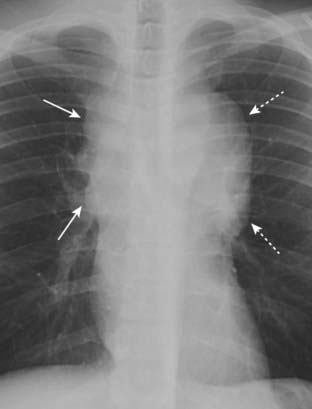

Figure 12-8 Middle mediastinal lymphadenopathy.

While lymphoma is the most likely cause of adenopathy in the middle mediastinum, other malignancies, such as small cell lung carcinoma and metastatic disease, as well as several benign diseases, can produce these findings. This patient has a mediastinal mass demonstrated on both the frontal (A) (solid white arrows) and lateral (B) views (solid black arrow). The mass is pushing the trachea forward (dotted white arrow) on the lateral view. The biopsied lymph nodes in this patient demonstrated small cell carcinoma of the lung.

Other malignancies that produce mediastinal lymphadenopathy include small cell lung carcinoma and metastatic disease such as from primary breast carcinoma (Fig. 12-8).

Benign causes of mediastinal lymphadenopathy include infectious mononucleosis and tuberculosis, the latter usually producing unilateral mediastinal adenopathy.